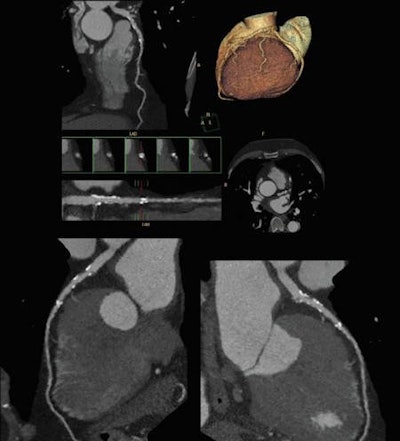

Cardiac CT angiography performed at lower x-ray dose can help to characterize cardiovascular disease. Image courtesy of Philips Healthcare.Looking at an occlusion with angiography, you have no idea about what is going on behind that occlusion, but CT can visualize the amount of plaque and also the coronary lumen, according to Achenbach. With a high negative predictive value consistently ranging between 98% and 99% in different studies, CT allows cardiologists to confidently rule out stenosis, giving it a high prognostic value. The modality has a close-to-zero event rate after ruling out stenosis, allowing 84% of patients to be sent home without a single recorded cardiac event among this population over the next 30 days.

Cardiac CT images look stunning, but the technique is not perfect. This CT scan used the Flash Spiral Cardio facility of the Somatom Definition system. A 0.9 mSv dose was needed to show the fine details. Image courtesy of Siemens Healthcare.Meier concedes CT radiation levels have been greatly reduced, but the images produced at 5 mSv do not lead to diagnostic confidence. As a result, patients often undergo a nuclear perfusion study at 9 mSv or possibly even a second examination to validate findings.